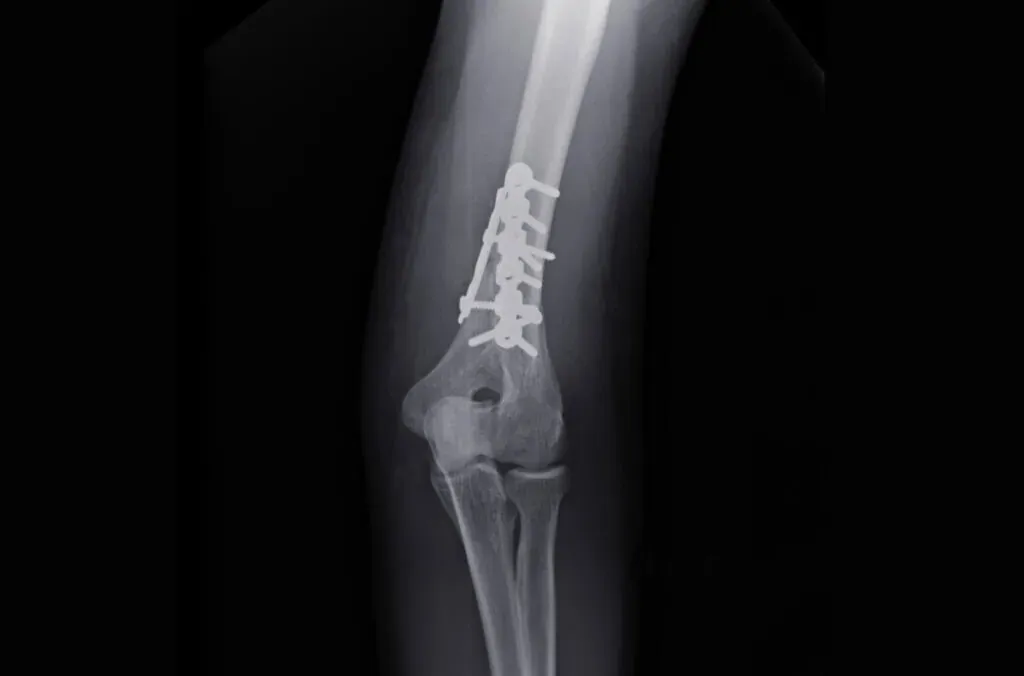

Natomiast w przypadku bardziej skomplikowanych złamań, takich jak złamania wieloodłamowe, które wymagają operacji, pełny powrót do zdrowia może zająć znacznie więcej czasu. Czas leczenia pooperacyjnego dla złamań końca bliższego kości ramiennej może wynosić od 6 do 20 tygodni. Warto zauważyć, że rehabilitacja powinna być rozpoczęta jak najwcześniej, aby zminimalizować ryzyko osłabienia mięśni i wspierać proces gojenia.